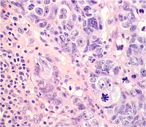

A case of large cell neuroendocrine carcinoma of the bladder with prolonged spontaneous remission

Vincent Chong and others

Journal of Surgical Case Reports, Volume 2017, Issue 5, May 2017, rjw179, https://doi.org/10.1093/jscr/rjw179